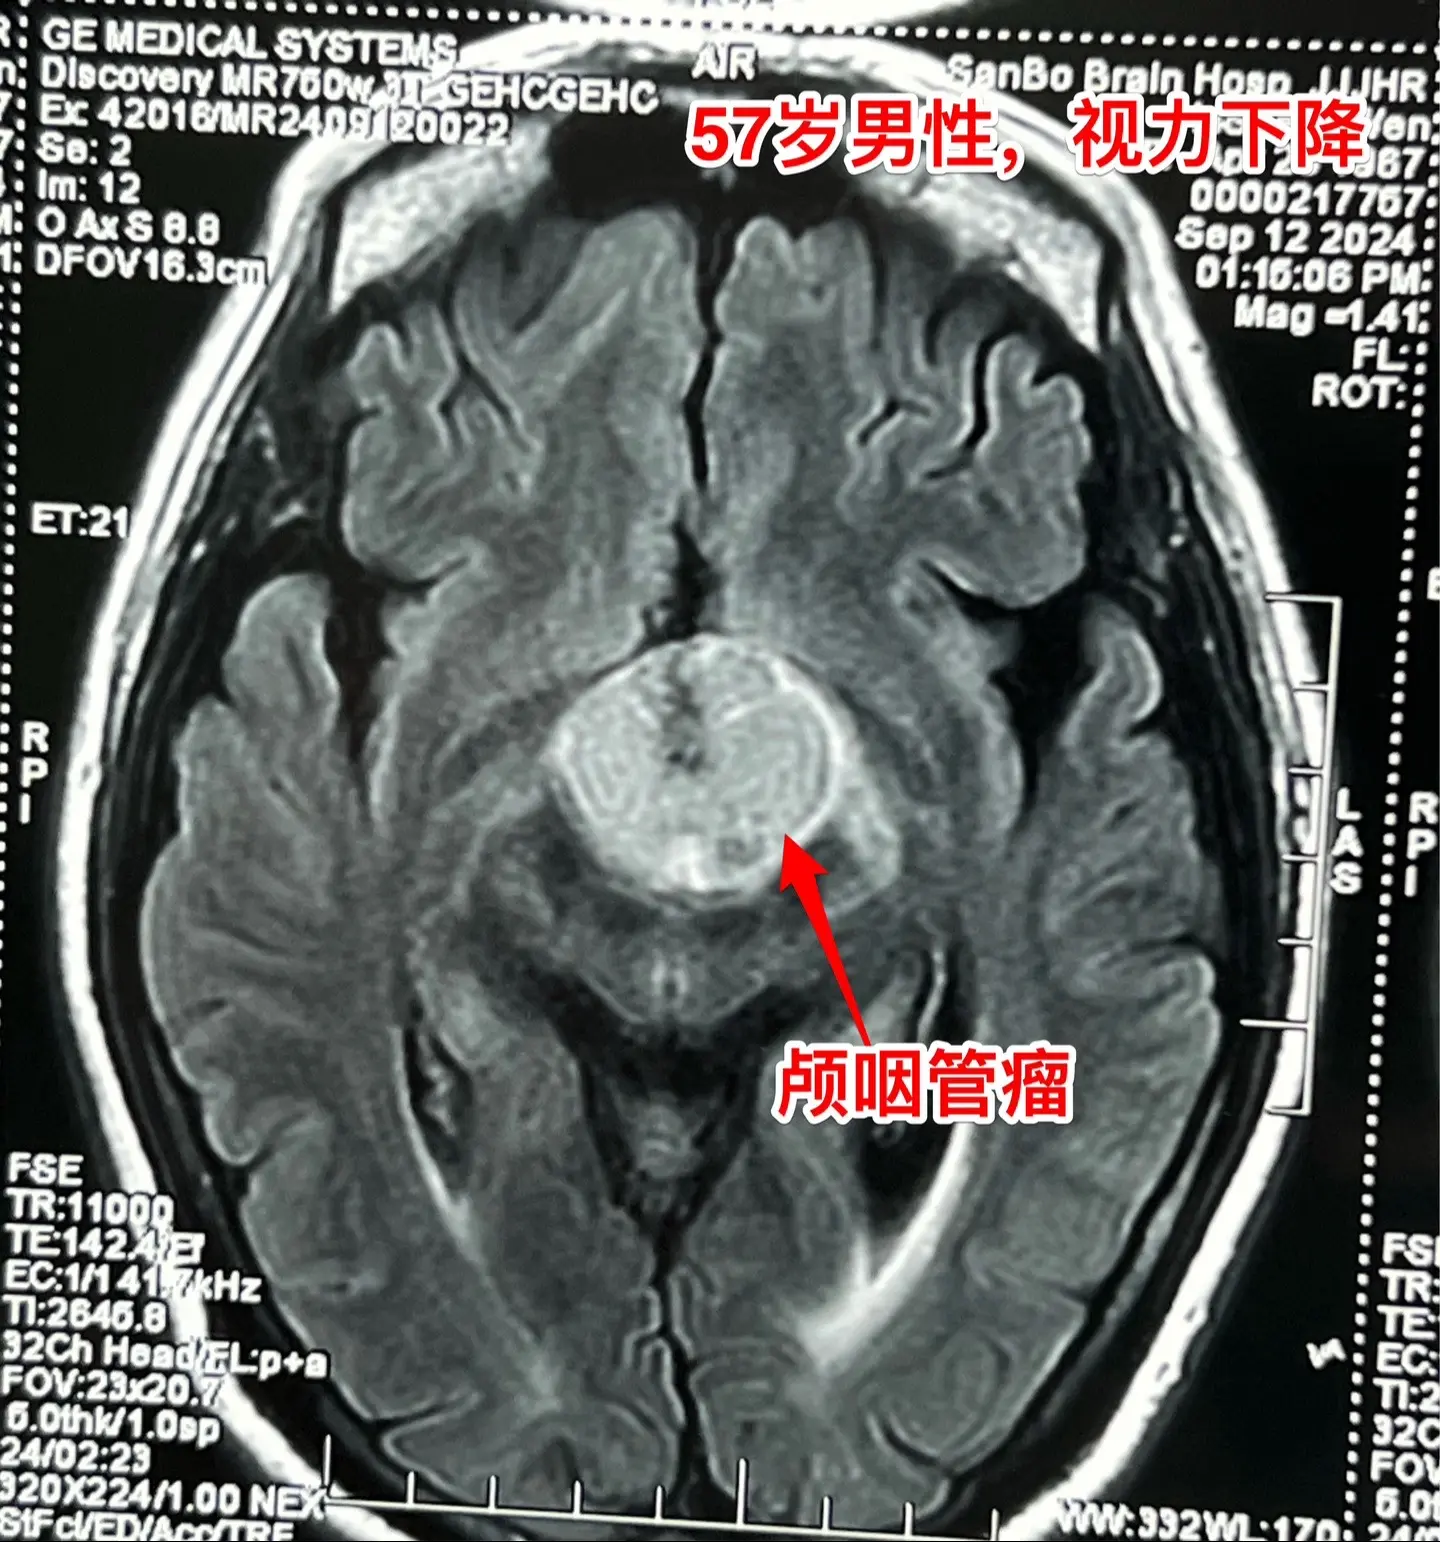

57岁男性,颅咽管瘤导致视力下降。病人因视力下降、消瘦到外院检查发现颅...